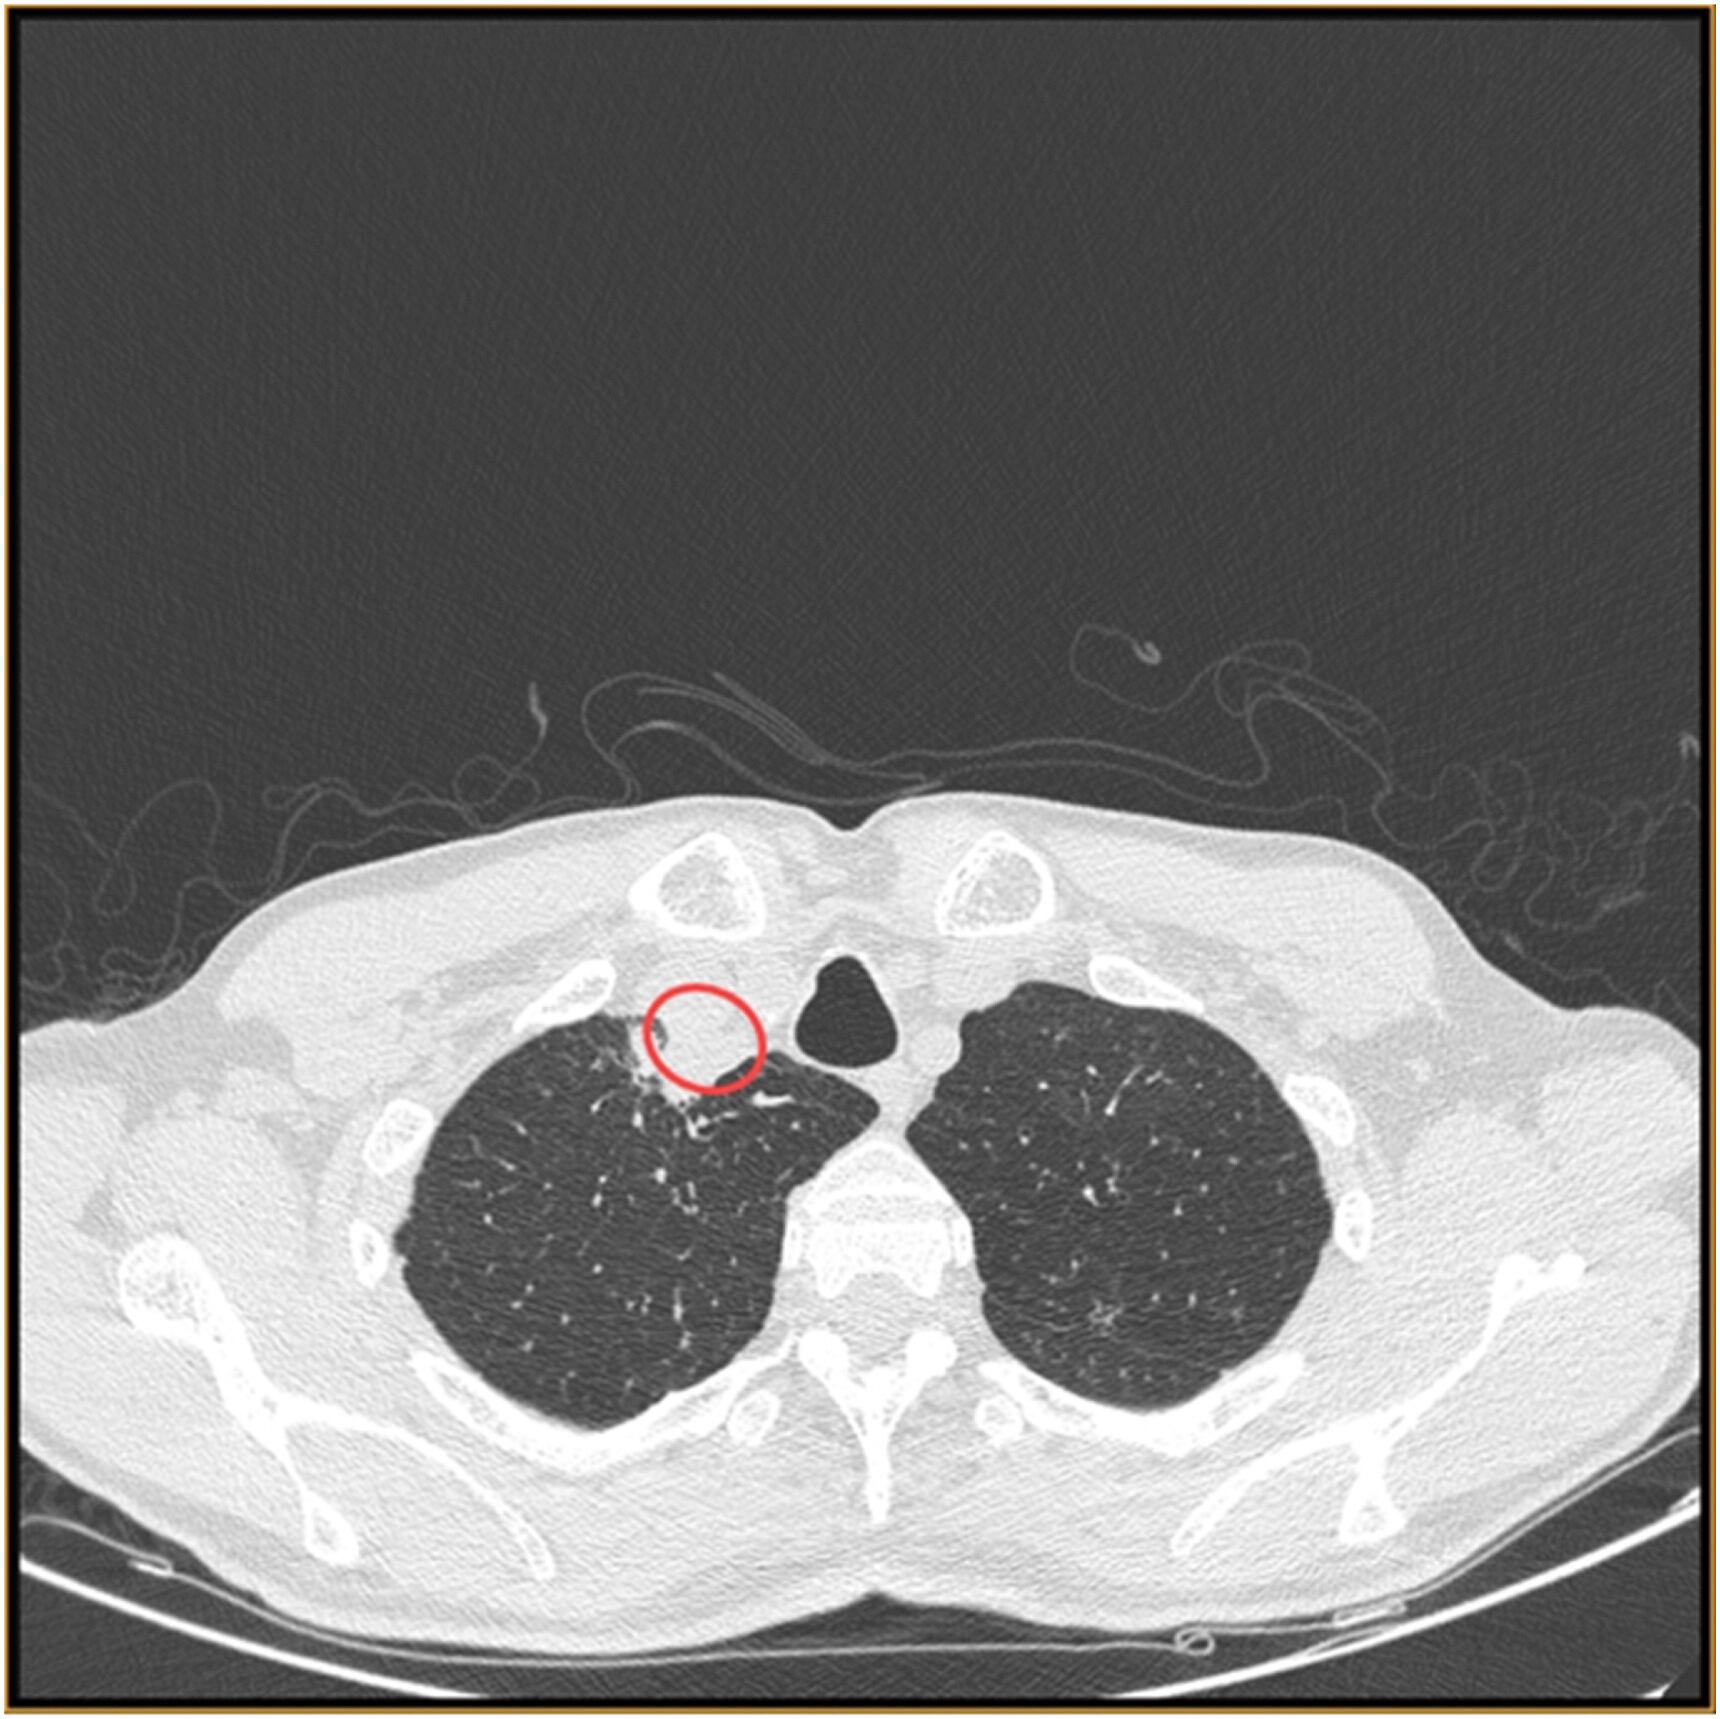

También el portal Science Direct compartió que en el estudio Absceso paratraqueal por hongo vegetal Chondrostereum purpureum, primer reporte de caso de infección humana, a través de una tomografía computarizada del cuello, se demostró la presencia de un paraabsceso traqueal.

De ahí se aspiró un pus, que fue enviado para las investigaciones pertinentes. Además de otros procesos, se evidenció el cultivo de pus en agar dextrosa Sabouraud (SDA) creció una colonia pastosa cremosa con pigmentación de color beige en el reverso lateral tras 4-5 días de incubación tanto a 25 ◦C como a 37 ◦C.

Luego, con los resultados del Centro colaborador de la OMS para Referencia e Investigación sobre Hongos, se identificó que se trataba de Chondrostereum pur- pureum por secuenciación de ADN. El examen histopatológico del material de aspiración reveló células inflamatorias mixtas, neutrófilos y algunas células endobronquiales en un fondo necrohemorrágico.